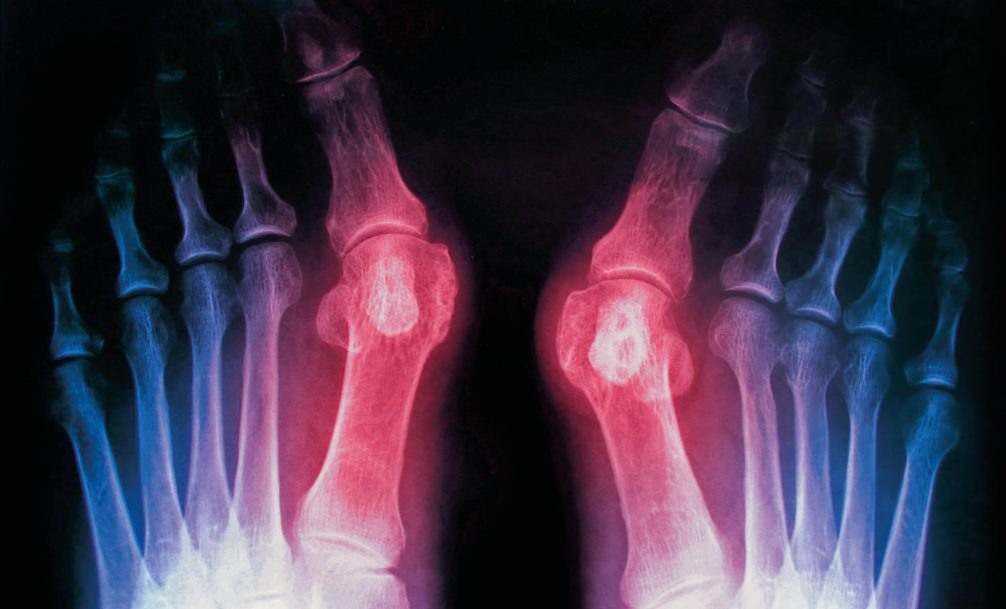

Вальгусная деформация стопы – это не просто «косточка». Это сложная ортопедическая патология, при которой происходит отклонение первой плюсневой кости стопы внутрь, а большого пальца – наружу. Образующийся при этом бугорок – это не нарост, а головка этой самой плюсневой кости, которая из-за деформации выходит из сустава.

-Ранняя стадия. Угол отклонения пальца менее 20°. Появляется небольшая шишка, покраснение, усталость ног к концу дня.

-Средняя стадия. Отклонение 20-35°. Боль становится постоянной, формируются натоптыши и мозоли, подобрать обувь все сложнее.

-Тяжелая стадия. Угол более 35°. Палец «залезает» на соседние, стопа сильно деформирована, боль мучительная и постоянная, даже в покое. Развивается хронический бурсит (воспаление суставной сумки).

Вальгусная деформация стопы